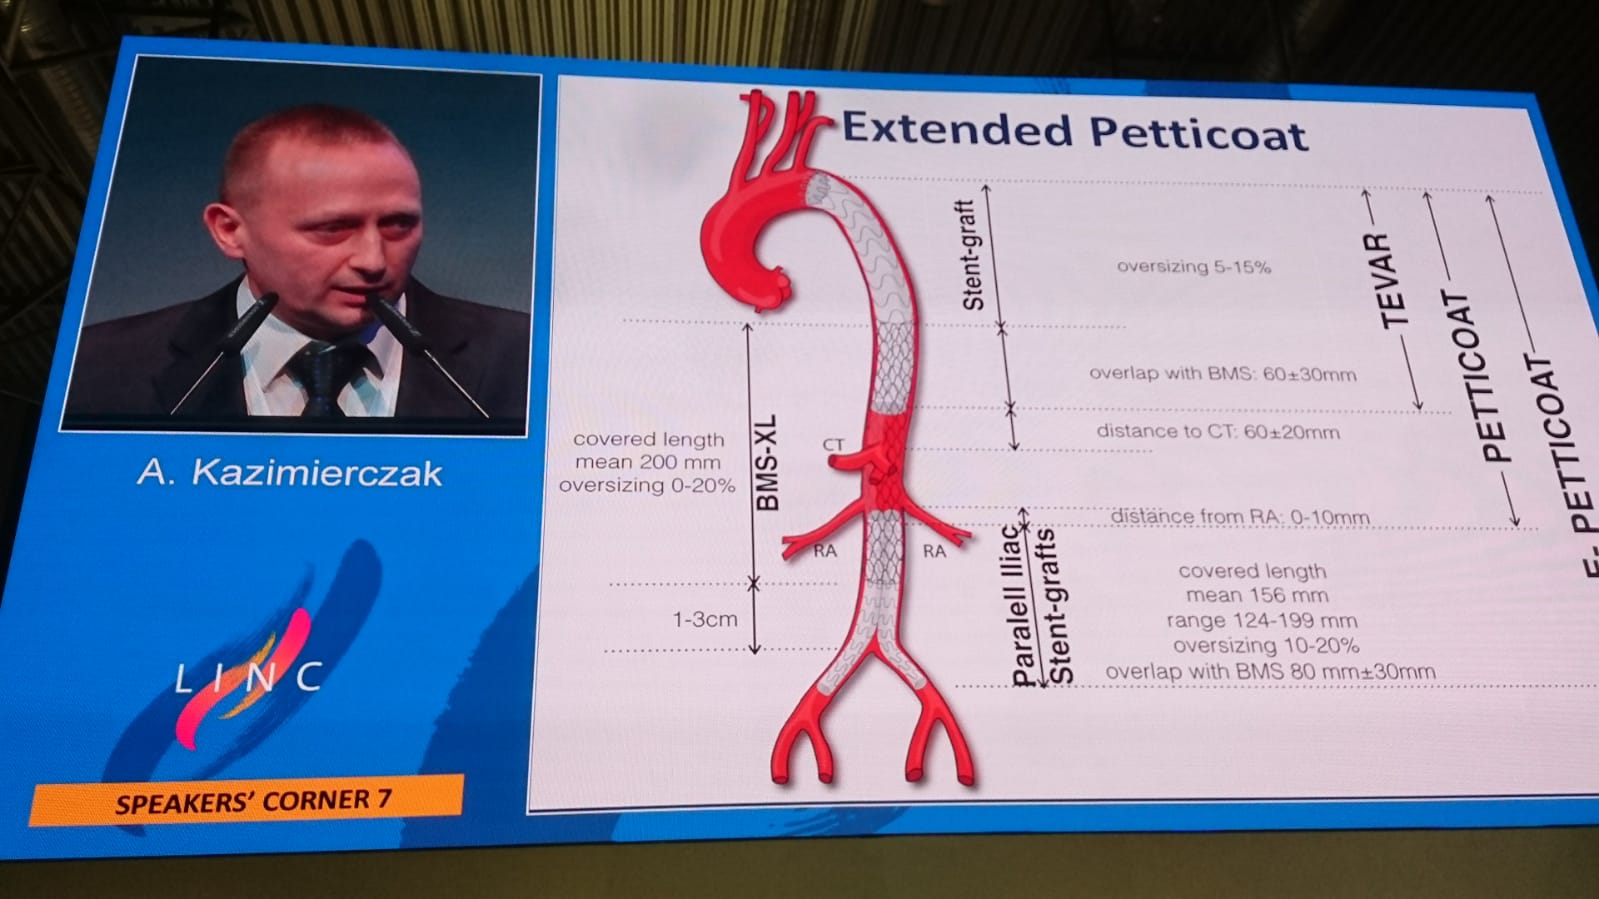

Nasi chirurdzy naczyniowi z Aortic Team znów pierwsi w kraju!

2022-11-07Lekarze Kliniki Chirurgii Naczyniowej, Ogólnej i Angiologii naszego szpitala dokonali pierwszego w kraju, całkowicie przezskórnego wszczepienia modyfikowanego stent-graftu. Była to operacja ratująca życie, a pomocna przy tym - technika druku 3D.

Dostępy całkowicie przezskórne (bez cięcia skóry) wykonuje tylko kilka ośrodków w Polsce i jest to metoda coraz częściej preferowana, ale głównie do mniej skomplikowanych przypadków. Tym razem do szpitala na Pomorzanach trafił 75-letni pacjent z objawowym tętniakiem okołotrzewnym (aorty piersiowo-brzusznej) - bolesnym, grożącym pęknięciem, a zatem stanowiącym zagrożenie życia. Dodatkowo chory nie miał szans na skorzystanie ze standardowego stent-graftu branchowego (z doszywanymi „rękawkami” na naczynia) czy fenestrowanego (z wyciętymi „okienkami” na naczynia) zamawianego u producenta z powodu występujących u niego dodatkowych naczyń, odchodzących od aorty (osobne ujście tętnicy wątrobowej). Nie mógł też czekać na wyprodukowanie stent-graftu szytego dla niego na miarę, bo trwałoby to 8-12 tygodni, a bolesność tętnika świadczyła, że rychło pęknie. Groziło to śmiercią pacjenta.

Leczenie stent-graftami modyfikowanymi jest w domeną naszych lekarzy Kliniki Chirurgii Naczyniowej, Ogólnej i Angiologii, którzy wypracowali wysokiej jakości standard postępowania w użyciu tej metody. Wykorzystując model aorty danego pacjenta, wydrukowany techniką 3D, modyfikują własnoręcznie, już na sali operacyjnej standardowe stent-grafty i dopasowują je indywidualnie do anatomii operowanego pacjenta. Po co? Bo mimo ogólnej takiej samej budowy każdego z nas, układ naczyń krwionośnych, ich budowa, odległości między poszczególnymi naczyniami różnią się u każdego człowieka. Dlatego dla efektywności działania wszczepianego, standardowego stent-graftu – proteza ta powinna być dopasowana do budowy chorego. Chirurdzy naczyniowi USK-2 są jedynym zespołem w Polsce, który tego typu zabiegi wykonuje rutynowo, również w przypadkach nagłych. Jednak taki sposób leczenia, jak i wszelkie inne zaawansowane procedury aortalne, wymaga licznych, często trudnych dostępów naczyniowych (np. nacięć w pachwinach, rękach i klatce piersiowej) – tj. cięć i operowania „na otwarto”. Dla chirurga taka operacja jest łatwiejsza, bo pole operacyjne jest widoczne jak na dłoni. Ale dla pacjenta dochodzenia do formy po takiej operacji jest długotrwałe, bolesne i mało komfortowe. Dlatego użycie przez szczecińskich lekarzy wyłącznie dostępu przezskórnego (bez cięcia) w leczeniu tętnika jest dużym krokiem na przód w chirurgii naczyniowej, a fakt, że to pierwszy tego typu zabieg w Polsce to ogromny sukces naszych „naczyniowców” i świadczy o ich doskonałej technice operowania.

„Modyfikacja stent-grafu naszą, ‘szczecińską metodą’ pozwoliła na pokonanie technicznych trudności, dostosowanie protezy do chorego i wykonanie zabiegu „od ręki”. Zastosowaliśmy modyfikację stent-graftu z okienkami na cztery naczynia trzewne - mówi dr hab. n. med. Arkadiusz Kazimierczak, który wraz z dr. n. med. Pawłem Rynio operował mężczyznę. „Wykonanie przezskórne - dwa dostępy do tętnicy podobojczykowej na klatce piersiowej i obu udowych w pachwinach, zamiast jak dotychczas czterech - pozwoliło na zminimalizowanie urazu operacyjnego tak, że chory był w pełni uruchomiony już w pierwszej dobie po zabiegu i zapytał o termin wypisu ze szpitala – dodaje dr Paweł Rynio. Operacja odbyła się 20 września.

Obaj lekarze są członkami szczecińskiego Aortic Teamu, zespołu chirurgów naczyniowych i kardiochirurgów stosujących nowatorskie metody leczenia w przypadku tętniaków. Zespół planuje rozszerzenie wskazań do zabiegów całkowicie przezskórnych w leczeniu patologii łuku aorty. Pierwsze próby z ograniczeniem urazu operacyjnego w tym zakresie zostały już podjęte w przypadku innej operowanej chorej. Tym razem zastosowano dwa małe cięcia przy wymianie całego łuku aorty, zamiast jak dotychczas pięciu. Pacjentka również jest w dobrym stanie.

Tłumacząc obrazowo - tętniakiem aorty nazywany nadmierne (o ponad 50%) poszerzenie aorty, która jest największą tętnicą w ciele człowieka. Może ono występować na każdym jej odcinku, ale najczęściej występuje w części brzusznej. Przyczyną ich powstania jest odkładanie się blaszek miażdżycowych, nadciśnienie tętnicze, nadmierny, gwałtowny wysiłek czy uraz, czasem także wrodzone nieprawidłowości w budowie naczynia. Ryzyko wystąpienie tętniaka aorty brzusznej wzrasta z wiekiem i jest szczególnie wysokie u mężczyzn około 65. roku życia. Szczególnie niebezpieczne są tętniaki bezobjawowe, które w każdej chwili mogą grozić pęknięciem i prowadzić do zgonu chorego.